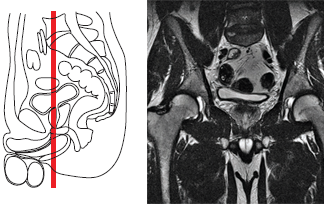

Магнитно-резонансная томография (МРТ) органов малого таза проводятся после предварительного ультразвукового обследования этого анатомического региона.

- высокая разрешающая способность — на магнитно-резонансной томографии (МРТ) органов малого таза можно увидеть объекты размером до нескольких миллиметров и есть возможность получать изображение в любой плоскости;

Желательно проводить исследования органов малого таза на магнитно-резонансном томографе (МРТ) с напряженностью магнитного поля от 1,5 Тесла. В некоторых случаях Вам могут предложить введение внутривенное контрастного вещества для оценки характера процесса и его распространенности.

Магнитно-резонансное исследование (МРТ) органов малого таза 3,0 Т (тесла) не требует специальной подготовки больного, однако как мужчинам, так и женщинам желательно некоторое (не тугое) заполнение мочевого пузыря, то есть перед исследованием не рекомендуется опорожнять мочевой пузырь.